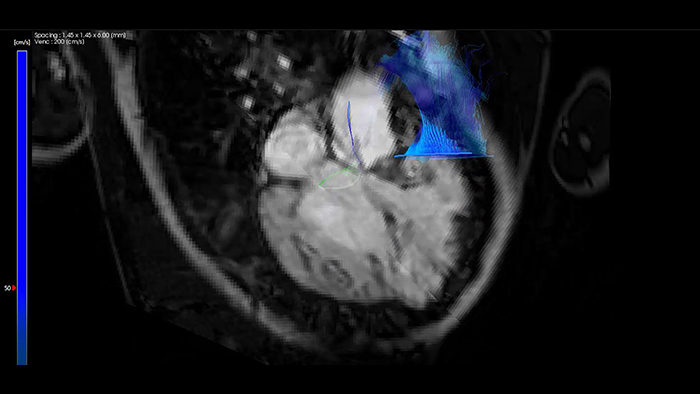

IntelliSpace Portal MR Caas 4D flow in Tetralogy of Fallot

ASD closure with EchoNavigator live fusion